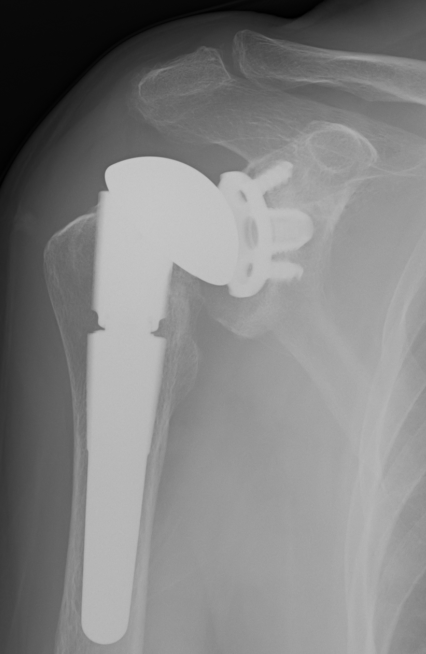

Augmented glenoids

Posterior-wedged augment Stepped augment Full wedged augment

Advantages

- good version correction

- preserves bone stock

- CT evaluation of standard glenoid v posterior stepped augmented glenoid

- posterior stepped glenoid better at correcting version in type B2 and B3

- difficult to restore ML joint line position with both with central glenoid erosion i.e. type A2 or B3

Sheth et al. Should Elbow 2022

- systematic review of augmented glenoid components

- 9 studies and 312 patients

- increased radiolucency seen with 16 wedges and 5 mm steps